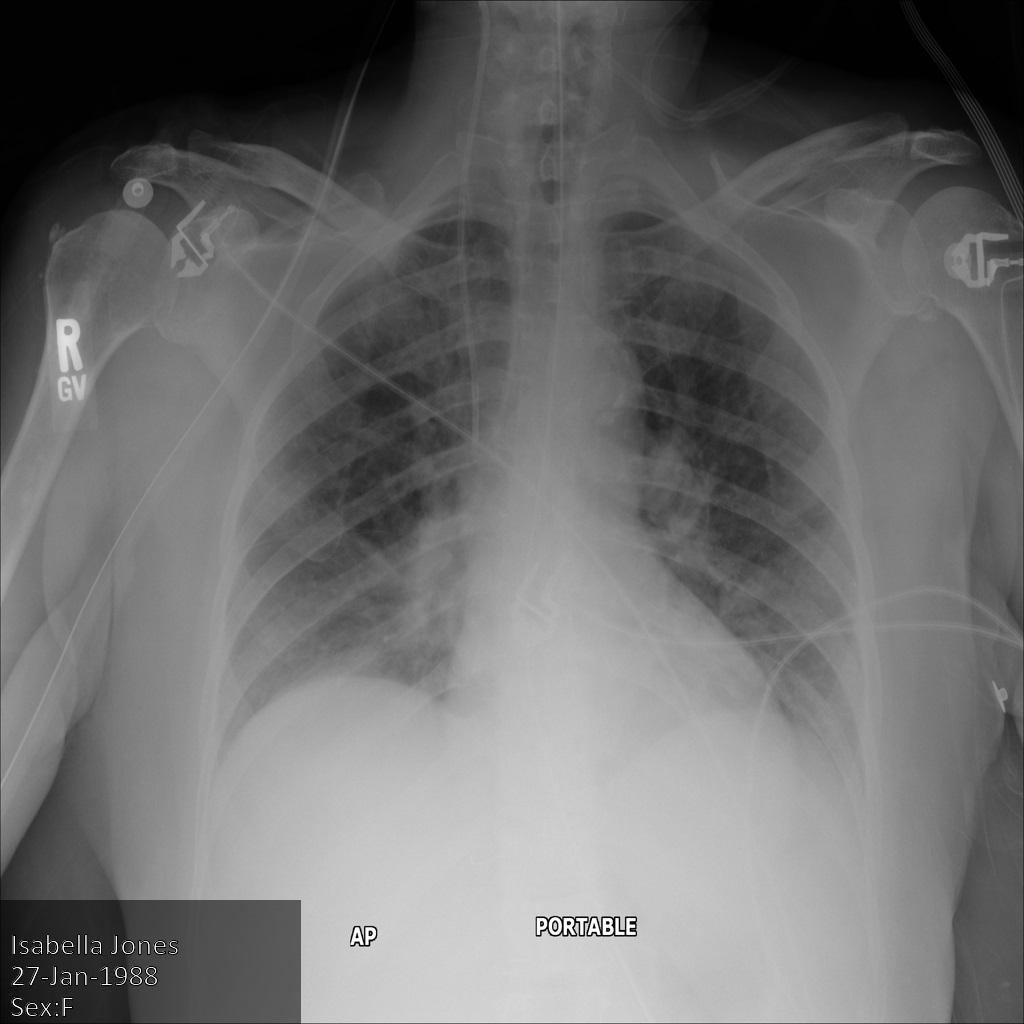

En cada una de las siguientes secciones, se proporcionan ejemplos de cómo desidentificar datos de DICOM mediante varios métodos. Se proporciona un resultado de la imagen desidentificada en cada muestra. En cada muestra, se usa la siguiente imagen original como su entrada:

Puedes comparar la imagen de salida de cada operación de desidentificación con esta imagen original para ver los efectos de la operación.

Después de enviar la imagen a la API de Cloud Healthcare, la imagen aparece de la siguiente manera. Mientras se ocultan los metadatos que se muestran en las esquinas superiores de la imagen, la información de salud protegida (PHI) quemado en la parte inferior de la imagen permanece. Para quitar también el texto quemado, consulta Oculta el texto quemado de las imágenes.